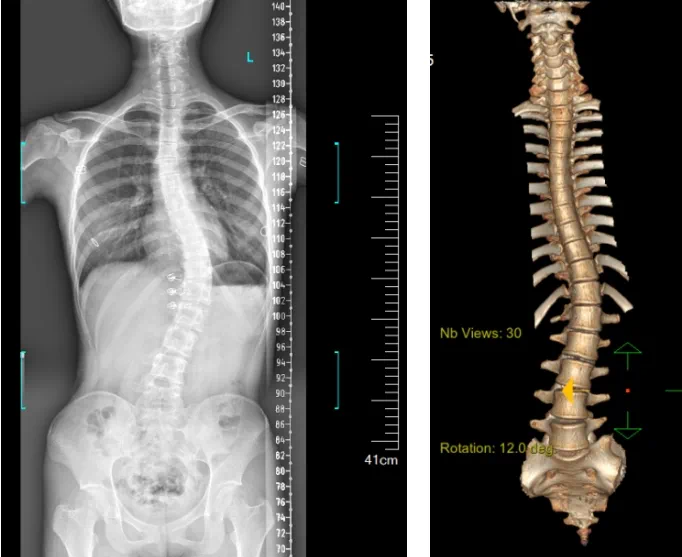

患者為一名16歲女孩,發(fā)現(xiàn)脊柱側(cè)彎1年,到南方醫(yī)院贛州醫(yī)院脊柱外科求診。經(jīng)查體,患者左右胸廓不對(duì)稱,雙肩等高,左肩胛骨隆起,背側(cè)呈“剃刀背”畸形,胸腰段棘突偏離正中線,胸腰段脊柱左側(cè)凸畸形;各棘突無壓痛及叩擊痛,右側(cè)腰部凹陷,胸腹及腰背部感覺正常。檢查發(fā)現(xiàn)患者特發(fā)性脊柱側(cè)彎,Lenke5C型,主胸彎51°。患者及家屬對(duì)外觀不滿意,為改善外觀及功能,要求手術(shù)矯形治療。

在與患者及家屬充分溝通后,針對(duì)患者的病情,脊柱外科團(tuán)隊(duì)在科主任陳榮春的指導(dǎo)下,經(jīng)過術(shù)前仔細(xì)評(píng)估,制定了機(jī)器人輔助下脊柱側(cè)彎矯形、植骨融合內(nèi)固定手術(shù)的治療方案,由郭朝陽(yáng)主任醫(yī)師主刀實(shí)施。

據(jù)悉脊柱側(cè)彎手術(shù)治療后可以保持軀干平衡,改善外觀并防止畸形進(jìn)一步發(fā)展。患者的生活質(zhì)量得到提高,進(jìn)而減少脊柱過度畸形可能帶來的疾病的發(fā)生率,外觀上的積極變化往往也能帶來患者心理與精神的積極變化。臨床上會(huì)綜合考慮患者的年齡、側(cè)彎程度、進(jìn)展趨勢(shì)、骨質(zhì)條件、鄰近節(jié)段情況、手術(shù)節(jié)段等因素,合理采用個(gè)性化的手術(shù)方式進(jìn)行治療。然而,由于脊柱神經(jīng)血管密布,手術(shù)操作相對(duì)復(fù)雜,手術(shù)難度高、風(fēng)險(xiǎn)大,傳統(tǒng)脊柱側(cè)彎的手術(shù)方式往往有較高的神經(jīng)或脊髓損傷風(fēng)險(xiǎn)。故此次科室決定開展機(jī)器人輔助導(dǎo)航下脊柱側(cè)彎矯形、植骨融合內(nèi)固定手術(shù)。術(shù)前,醫(yī)生團(tuán)隊(duì)在機(jī)器人多維度圖像融合智能手術(shù)規(guī)劃功能的輔助下,預(yù)先規(guī)劃了理想的置釘路徑。術(shù)中,天璣骨科手術(shù)機(jī)器人準(zhǔn)確遵循術(shù)前規(guī)劃,根據(jù)配準(zhǔn)結(jié)果,實(shí)時(shí)定位并準(zhǔn)確執(zhí)行置釘操作,所有導(dǎo)針均用電鉆置入,一次性成功,協(xié)助醫(yī)生順利完成手術(shù)。最終,在麻醉科、手術(shù)室密切配合下,歷時(shí)3小時(shí)成功完成側(cè)彎矯形術(shù),出血量?jī)H500ml。術(shù)后,患者恢復(fù)良好,大小便及下肢神經(jīng)運(yùn)動(dòng)感覺正常。